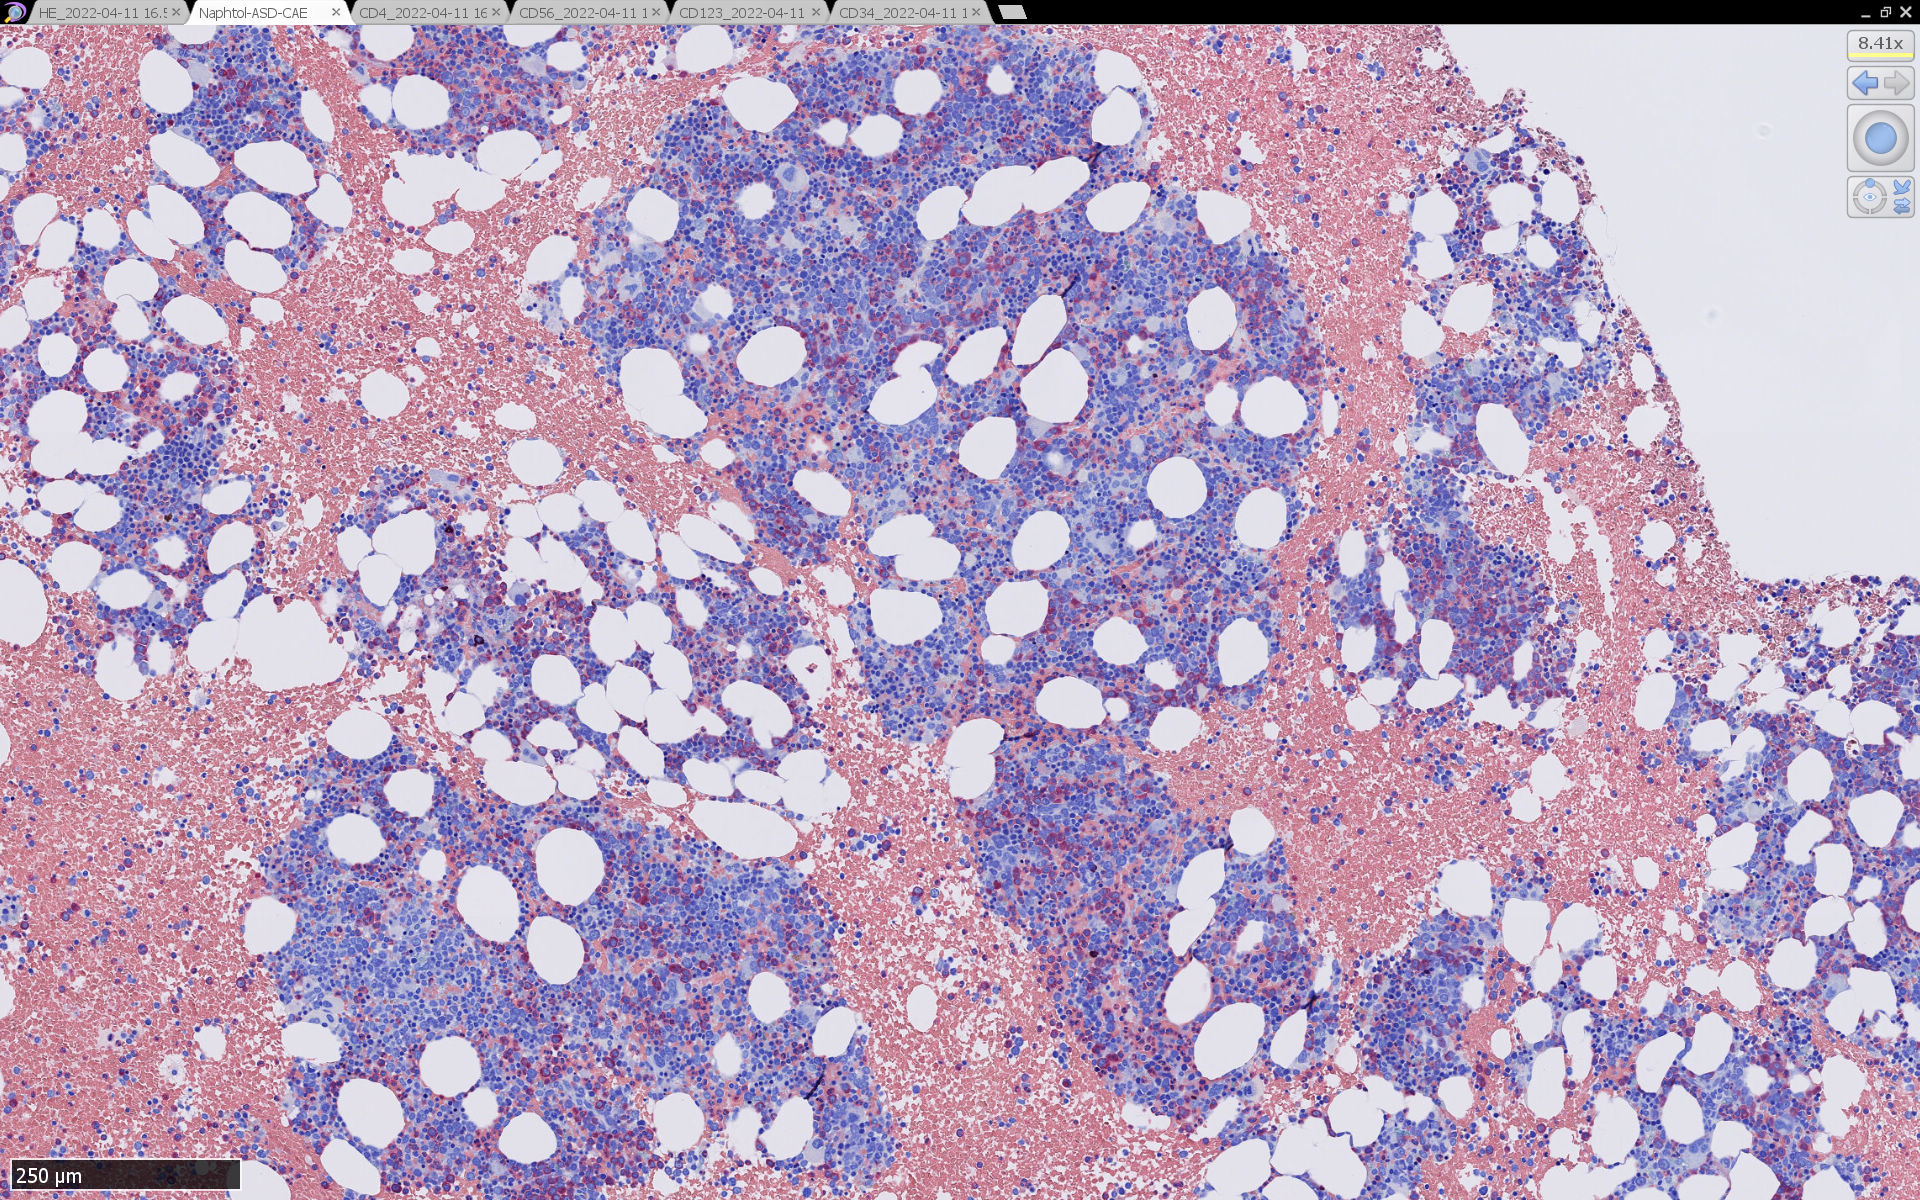

骨髄病理所見

HEでは腫瘍細胞の同定が難しい. 本症例は ASD-Giemsa染色を見ても, 腫瘍胞巣はよくわからなかった. 皮膚が先に診断がつき, 次いでBone marrowだったため, 免疫染色にすすめたが, Bone marrowが先だと診断に困ったかもしれない.

BPDCN骨髄病変の病理

症例骨髄に認められた異形成造血所見

Mgkは低分葉, 円形単核の細胞が多く, 分離円形核のMgkもみられた. 赤芽球はproerythroblstsのみの小集簇や孤在性出現あり. 成熟赤芽球が乏しい. 顆粒球系細胞も分葉好中球への分化像が少ない.

免疫染色では, HbFを発現する赤芽球の集簇巣が散見しているほか, p53陽性細胞が軽度に増加している. CD34陽性細胞増加はなし.CD42b染色でmicroMgkはみられなかった. 異形成造血が強く疑われる.